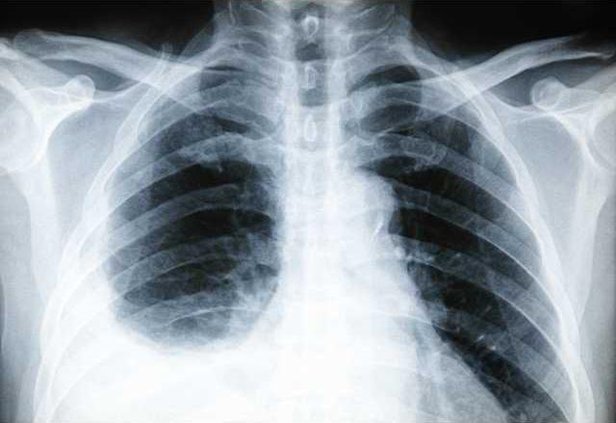

In a healthy body, the double-layered pleura lines the outside of the lungs and inside of the rib cage with a lubricating fluid in between its layers. When pleurisy happens, the tissue layers become inflamed and/or the fluid changes in consistency or amount.

In some cases of pleurisy, fluid builds up in the small space between the two layers of tissue, becoming a pleural effusion. When this extra fluid gets infected it's called an empyema, and is often accompanied by fever.